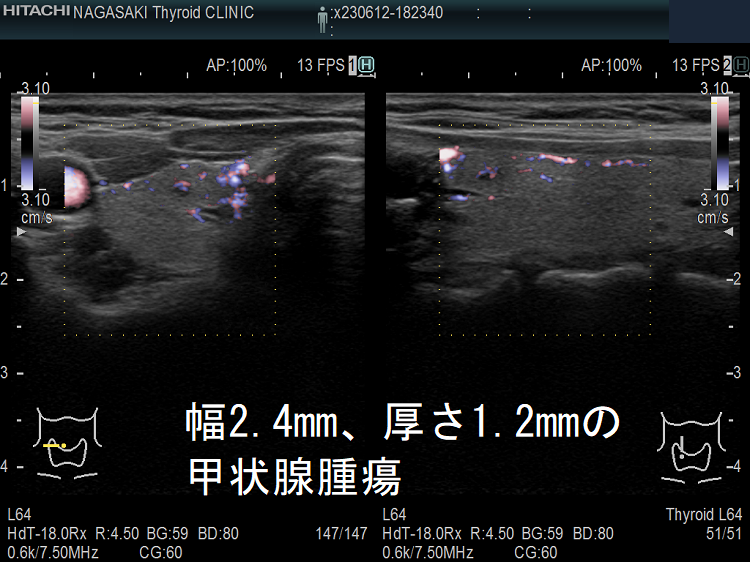

ケース② 幅2.4mm、厚さ1.2mmの甲状腺腫瘍

幅2.4mm、厚さ1.2mmの甲状腺腫瘍 超音波(エコー)画像

幅2.4mm、厚さ1.2mmの甲状腺腫瘍 超音波(エコー)画像;B-モードでは甲状腺のう胞(甲状腺嚢胞)甲状腺腫瘍か判別できません。

幅2.4mm、厚さ1.2mmの甲状腺腫瘍 ドプラーモード

幅2.4mm、厚さ1.2mmの甲状腺腫 超音波(エコー)画像 ドプラーモード;通常倍率でもドプラーモード[eFlow(イー フロー)]で内部微細血流を確認できるため、甲状腺腫瘍なのが判ります。